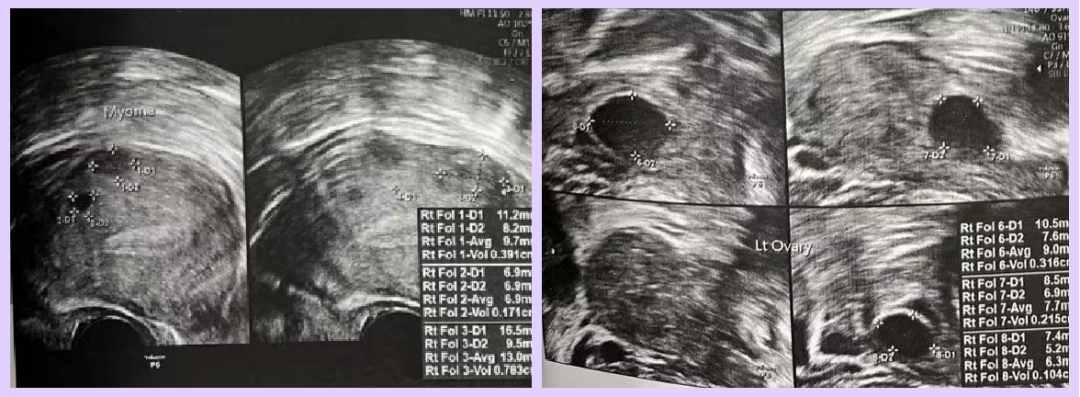

Both partners are of advanced reproductive age and had previously attempted IVF twice without success. After evaluation, the doctor diagnosed the female patient with diminished ovarian reserve (DOR) due to her age. Ultrasound revealed only 3 usable follicles (diameter > 4mm), indicating a significantly reduced ovarian reserve.

Controlled Ovarian Stimulation (COS)

- Day 2 of Stimulation (Thailand)

- Ultrasound Findings: 3 baseline follicles (<3mm: 2 follicles)

- Right ovary: 1 follicle (2mm)

- Left ovary: 4 follicles (9mm, 7mm, 6mm, 2mm)

- Day 5 of Stimulation (Thailand)

- Ultrasound Findings:

- Right ovary: 1 follicle (10mm)

- Left ovary: 3 follicles (14mm, 11mm, 10mm)

- Day 7 of Stimulation (Thailand)

- Ultrasound Findings:

- Right ovary: 1 follicle (11mm)

- Left ovary: 3 follicles (18mm, 15mm, 15mm)

- Day 9 of Stimulation (Thailand)

- Ultrasound Findings:

- Right ovary: 1 follicle (16mm)

- Left ovary: 3 follicles (23mm, 20mm, 18mm)